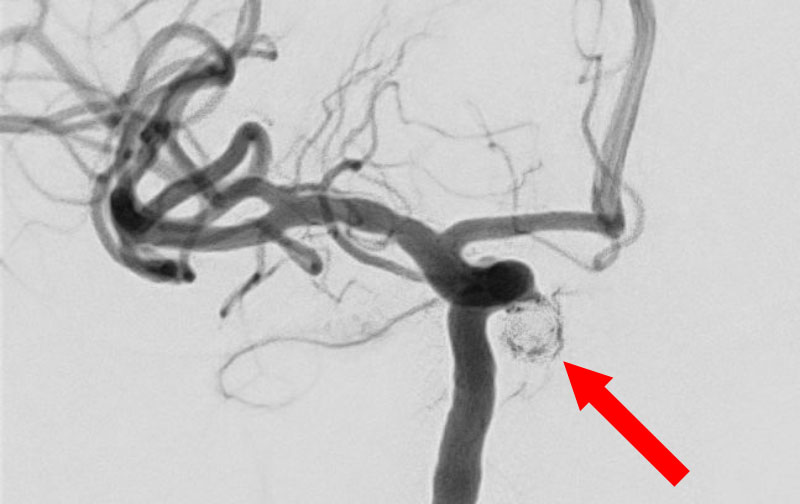

No.1593 手術前

No.1593 手術中